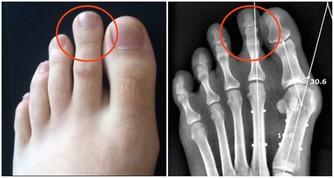

我們可以用手指在內外膝眼二個位置按揉,會發現手下有咕嚕咕嚕的感覺,膝關節過伸或勞累後疼痛,這就是膝蓋筋結。

把膝關節伸直看一看,如果膝眼是凹陷的,說明你的膝關節還可以,如果你的膝眼鼓起來了,摸到了硬硬的筋結,並且按著還有些疼,就說明膝關節退化的比較嚴重。

膝蓋有筋結,有問題光練膝蓋是不頂用的,股四頭肌是伸膝關節的力量來源,股四頭肌力量不夠,髕骨兩側就要出現筋結了,那時就不是打軟腿了,就該關節僵硬打不彎費勁了。所以說練好了這塊地方,膝蓋自然不疼。